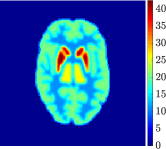

Figure 4, Figure 5, and Figure 6 show the mean images computed over the ten reconstructions obtained by the methods reg-AS-TR, reg-GN, and by the Matlab routine lsqcurvefit implementing a standard Trust-Region-Reflective least-squares algorithm [11, 10]. We used the noise-free IF and the perturbed IF with and of noise, respectively. Figure 7 contains mean and standard deviation values of the kinetic parameters computed over the ten reconstructions and over each one of the four homogeneous regions, for each one of the three noise levels on the IF.

In general, reg-AS-TR and lsqcurvefit seem to provide similar mean reconstructions, although uncertainties associated to lsqcurvefit are significantly bigger. On the other hand reg-GN seems to systematically underestimate the parameter values within region . Furthermore and as expected, for all methods the quality of the parametric reconstructions deteriorates with increasing noise levels; this is more clear from the and parametric images, probably due to the different sensitivities of the data with respect to the model parameters [37]. In reg-GN and lsqcurvefit some artifacts can be observed at the edges of the homogeneous regions, especially around region and region , whereas the effect of regularization in reg-AS-TR results in a reduced presence of artifacts while the structure of the regions is preserved. This general trend is confirmed by the error-bar plots of Figure 7. Finally, the frames in Figure 8 corresponding to reg-AS-TR show a significant improvement of the image quality with respect to what is provided by the other two approaches.